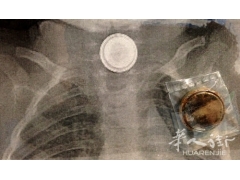

罗马4岁儿童突发腹痛,竟因误食了纽扣电池!

近日,罗马一名4岁儿童在家玩耍时,...

罗马一名4岁男孩误吞电池被医生检查发现

〓意大利华人街(微信订阅号:huarenjie...